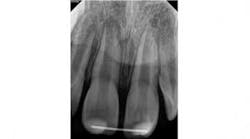

A 7-year-old male presented to my office following an accident that resulted in a horizontal root fracture of tooth No. 8. Upon examination, the general dentist had splinted the central incisors together using a rigid splint. Clinical testing on tooth No. 8 revealed that this tooth had a nonlingering response to cold and displayed slight tenderness to palpation. All other testing on teeth Nos. 7 and 9 was within normal limits (WNL). Radiographically, the apices of both central incisors were incompletely developed and a horizontal root fracture was noted at the junction of the coronal and middle third of the root on tooth No. 8 (figure 1). Due to the positive response to cold and lack of symptoms to percussion, bite, and palpation, I recommended retesting in three weeks and removal of the splint.